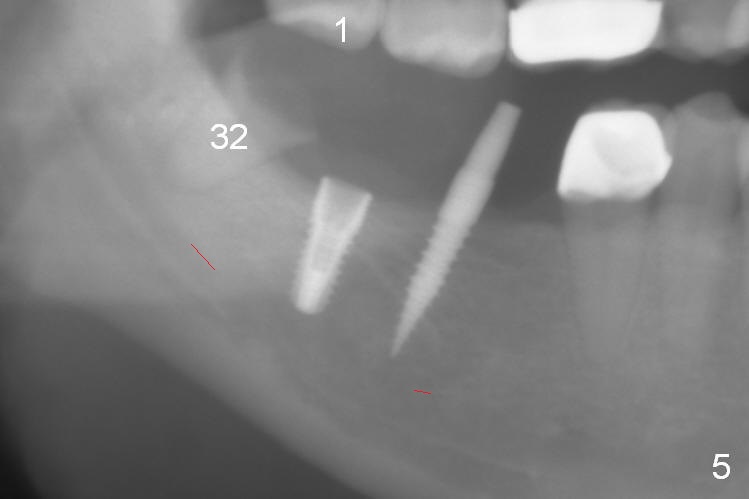

A preop photo shows different shape of pontics at #30 and 31 (Fig.1 <), suggesting different width of the edentulous ridge. Two of 8 mm parallel pins are inserted for position and trajectory (Fig.2 (red dashed line: the superior border of the Inferior Alveolar Canal). When they are removed from the osteotomy sites, the narrow ridge at #30 is shown (Fig.3). A 3x12 mm 1-piece implant is placed at #30, while a 4.5x10 mm 2-piece one at #31 (Fig.4,5). It appears that it is necessary to place an implant at #32, since the tooth #1 is present (Fig.5). The suggestion is rejected by the patient due to finance. After extraction of the tooth #32 and insertion of collagen plug, an immediate splinted provisional is fabricated to cover the #32 socket as well (Fig.6). The provisional is modified (to remove the portion that covers #32 socket) 3-4 weeks postop.

The patient returns for final restoration 3 months postop; bone resorption around the 1-piece implant is minimal (Fig.7). The definitive restoration is also splinted. The latter is further justified when the implant at #30 is found to be distal prior to cementation (Fig.8 *). It appears that implant spacing at the root level is more critical than parallelism, as compared to Fig.7. Let us improve this aspect. Bone loss around the implants remains minimal 7 months post cementation (Fig.9). It is the same 1 year 8 months post cementation (Fig.10), as compared to a cantilever FPD on the other side (Fig.11). The bone density around the implants at #30 and 31 increases 2 year 8 months post cementation (Fig.12).